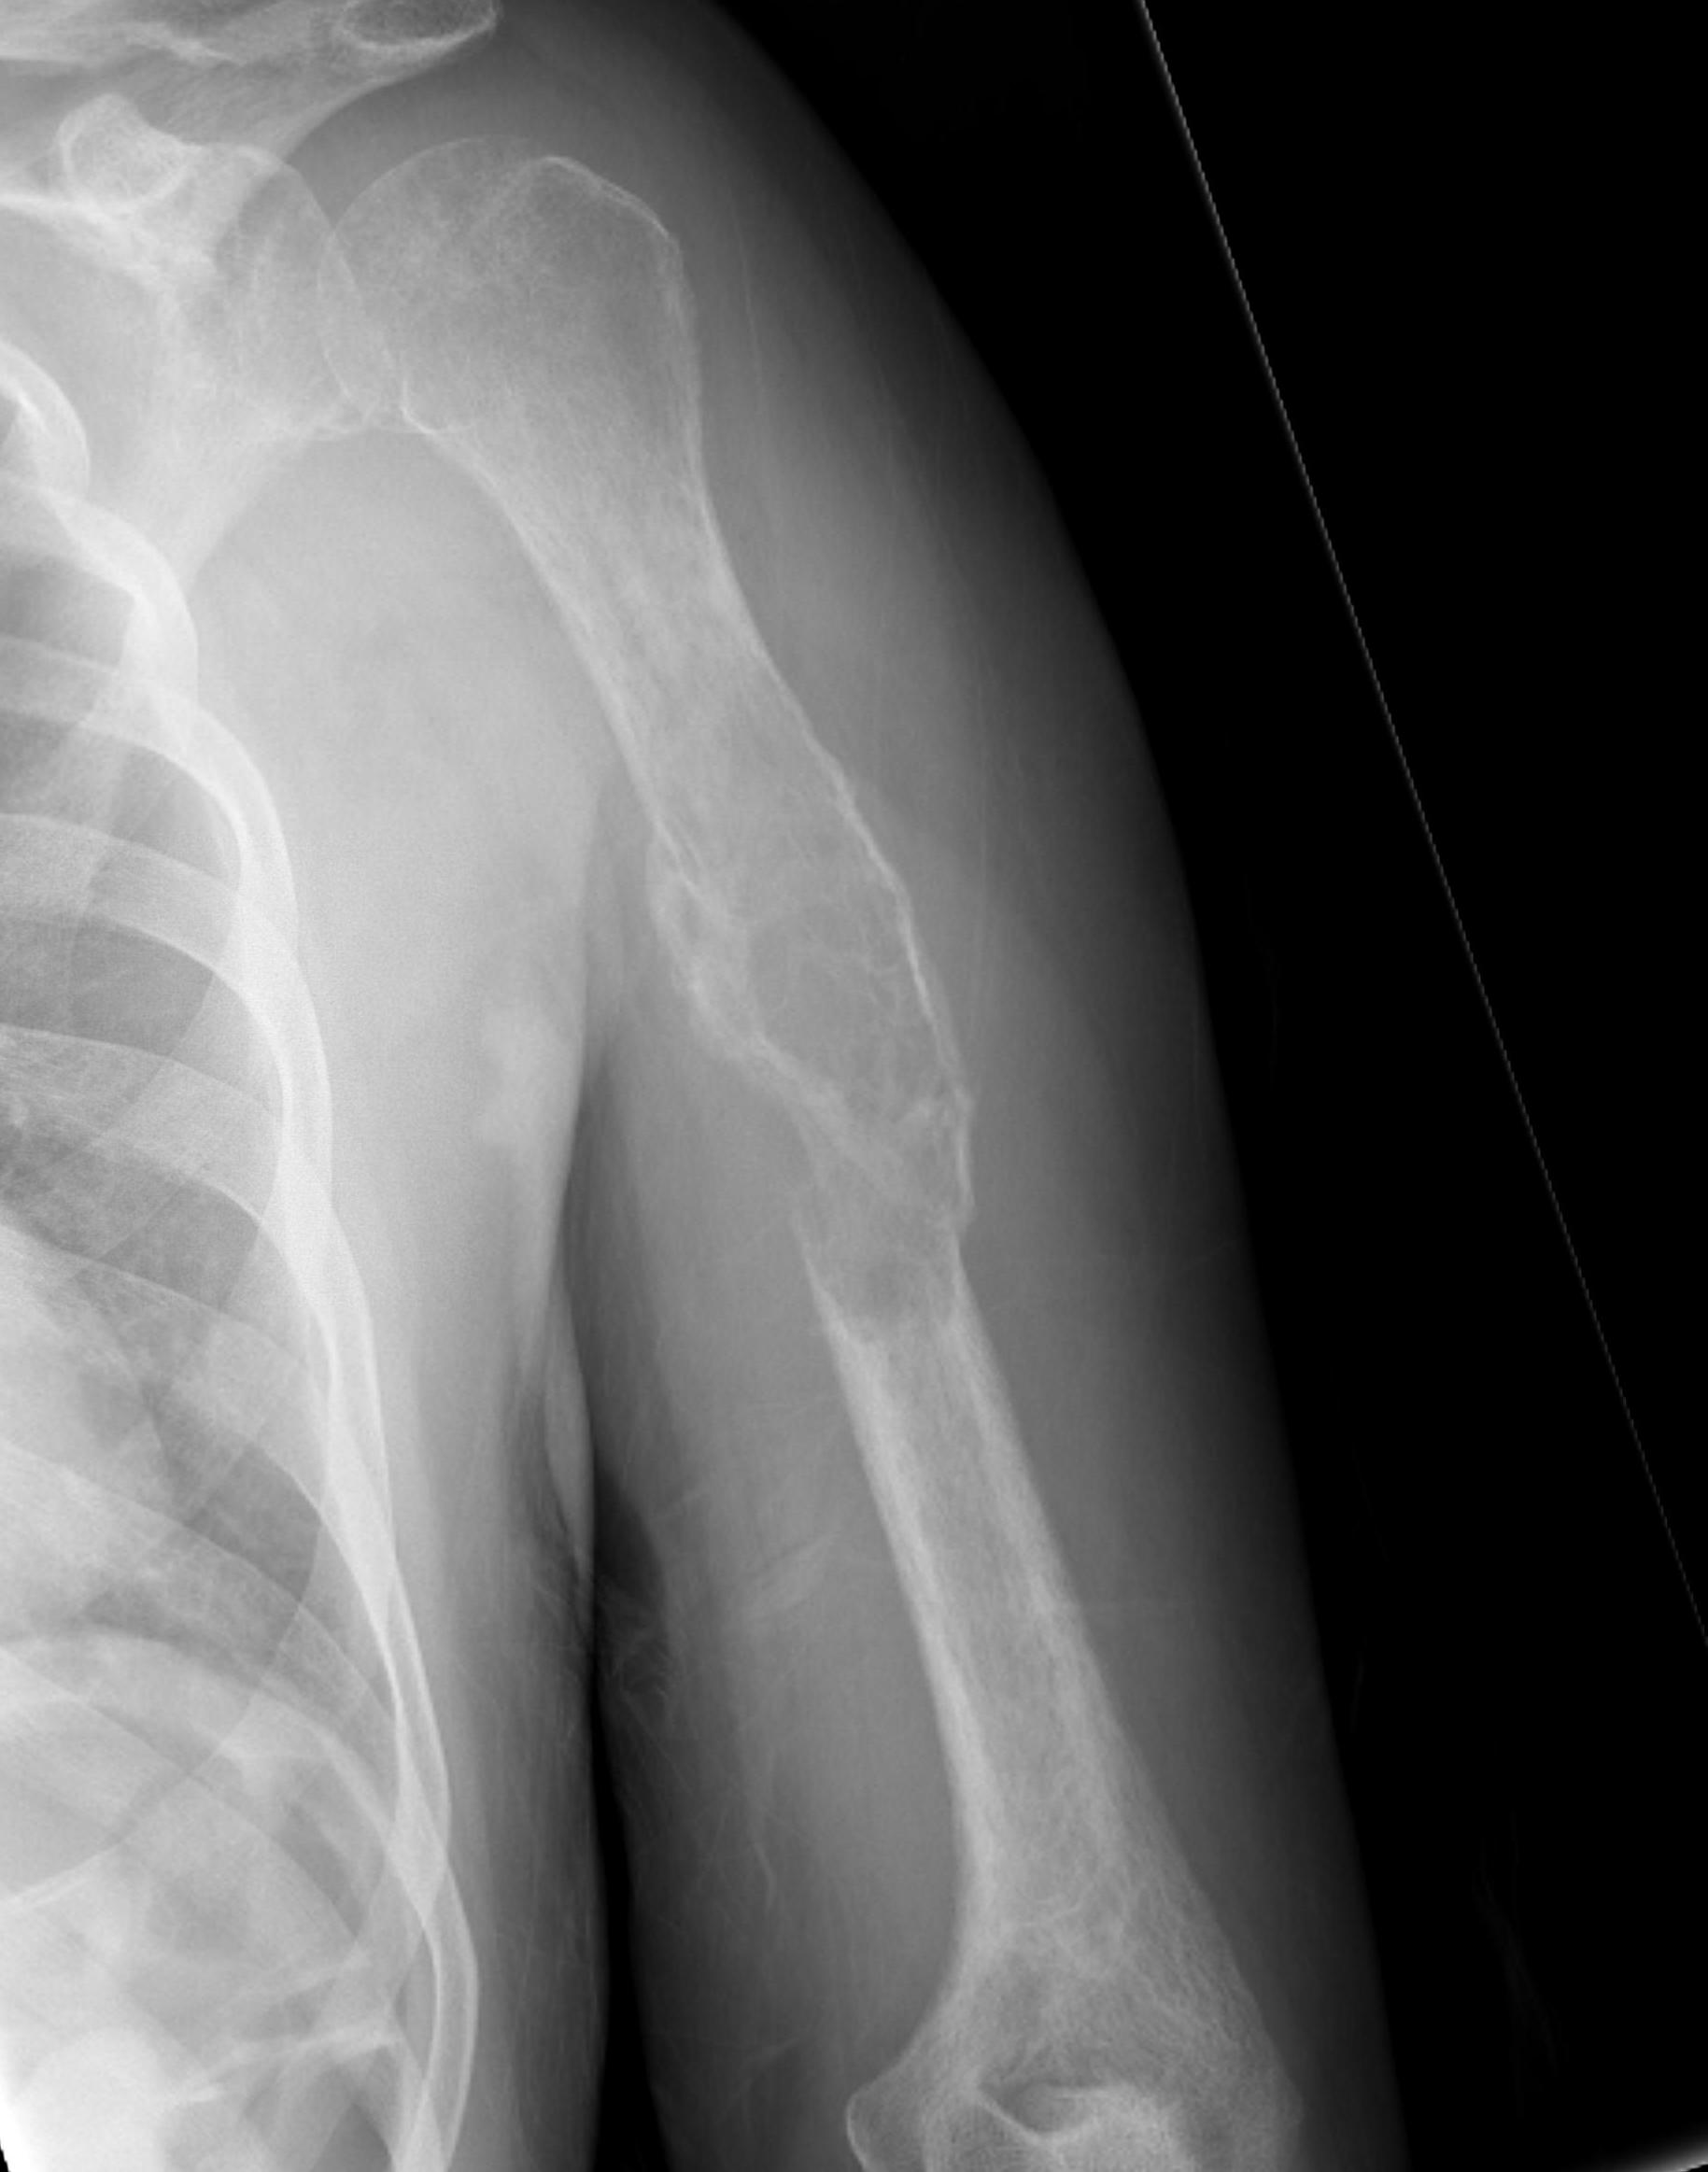

Humeral shaft

Options

Plate +/- cement

IMN +/- cement

Results plate

- 63 pathological humerus fractures

- all treated with cement + plate

- 11% reoperation rate

IMN versus plate

- stabilization of humerus pathological fracture

- broken implant 0% IMN at final follow up

- broken implant 14% plate + cement at final follow up